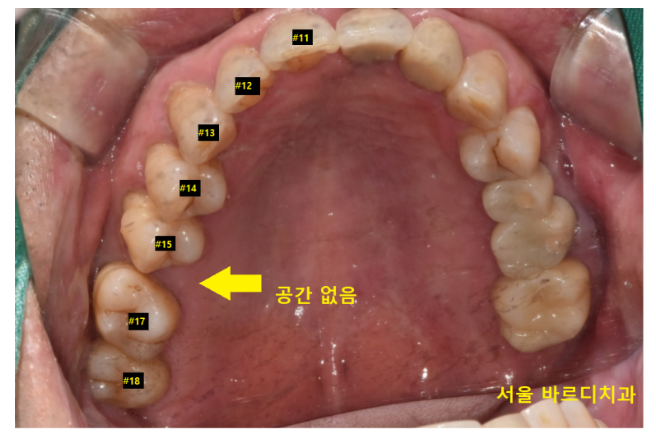

먼저 윗니 어금니

이제는 임플란트로 치료를 하고 싶어도

못하는 상황이 되었습니다.

11,12,13,14,15 적혀있는 것은 치아 번호입니다.

순서대로 있어야 하는데..

15 다음이 17이 있죠?

16 어금니가 안보입니다.

이 어금니가 오래전 발치된 것인데

시간이 오래 지나다 보니

치아 빠진 공간이 좁아졌습니다.

양 옆 치아(15번 17번)가 쓰러지기도 많이 쓰러졌고요.

임플란트를 심을 수 있는 공간이 나와야

나사가 들어가는데

전혀 공간이 보이지 않습니다.